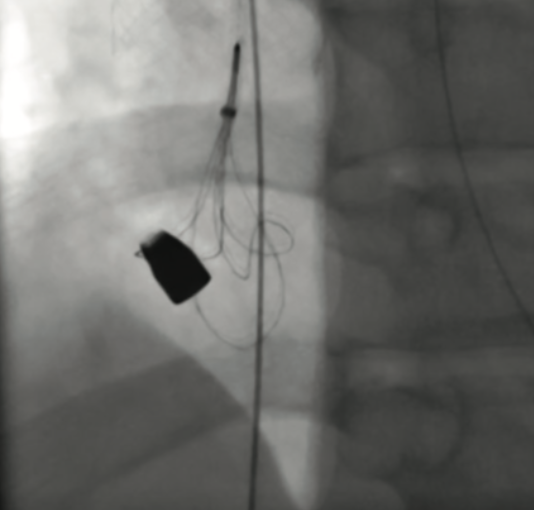

Next, the venotomy was dilated over the Amplatz wire, followed by placement of a 20F Protrieve sheath. The sheath was advanced to the right atrium, and the Protrieve funnel was deployed under fluoroscopic guidance to preclude migration of the bullet through the tricuspid valve. The sheath dilator was then retracted and removed. It was noted that the patient did not experience any cardiac ectopy and remained in normal sinus rhythm following deployment of the Protrieve funnel.

Subsequently, an 18-30 mm EN Snare Endovascular Snare System (Merit Medical) was assembled and advanced through the Protrieve sheath. Under fluoroscopy, the bullet was seen tumbling in the IVC at the ICAJ as the snare was utilized to capture it (Figure 3A, Video 1). The bullet was retracted through the mesh funnel and into the plastic sheath tip of the Protrieve sheath (Figure 3B, Video 2). The sheath was then retracted over the wire while tension was held on the bullet with the snare (Video 3). Fluoroscopy confirmed that the bullet did not move from the sheath tip and the bullet was then removed along with the sheath (Figure 3C-D). The sheath dilator was replaced into the venotomy site.

In the case described here, it was moderately difficult to determine the location of the bullet on CT scan due to imaging artifacts. However, it had been seen in multiple locations overlying the upper IVC and right atrium, suggesting an intravascular location that would allow mobility. Given the location, the operators were challenged to deploy the Protrieve sheath at a level that would prevent them from accidentally causing central embolization of the bullet. Although there was an initial preference to place the Protrieve funnel closer to the right atrial and IVC junction, it was ultimately deployed at the level of the mid-right atrium, which proved successful at preventing bullet migration into the right ventricle.